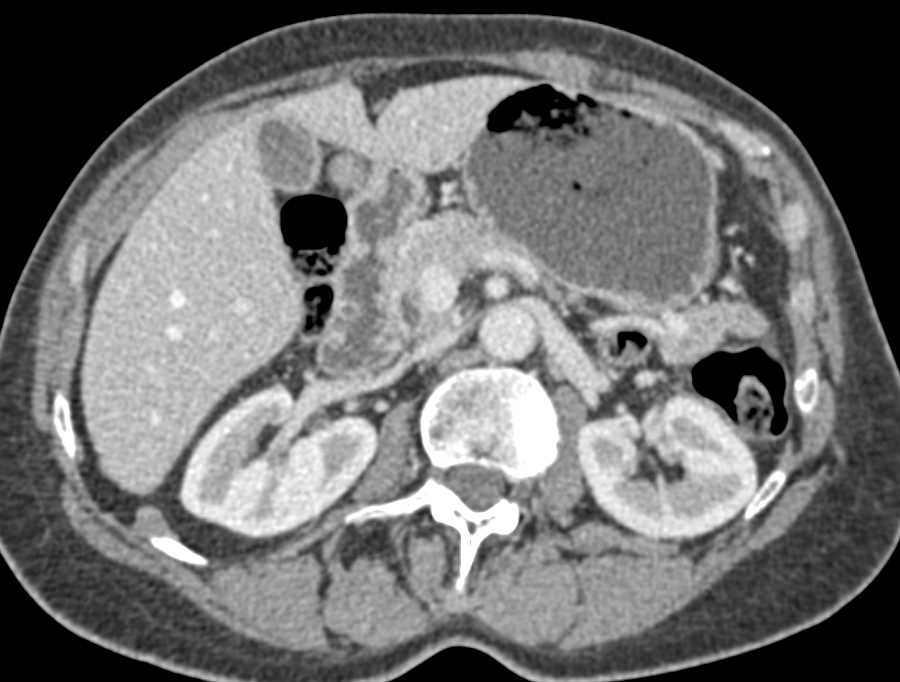

Metastatic Carcinoid Tumor with Vascular Implants